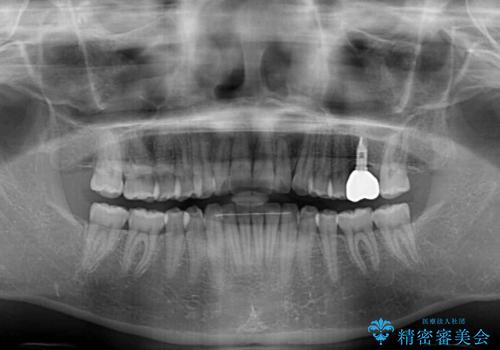

抜歯の上インプラントによる補綴治療を行うこととなりましたが、前歯の叢生も気になるとのことで並行して矯正治療を行うこととしました。

歯列不正は軽微であったので、インビザラインによる矯正治療とし、矯正治療中にインプラント埋入を行う予定としました。

痛みがないので、ボロボロのまま放置していましたが、抜歯後は汚れが溜まりにくくなりスッキリとしたようです。